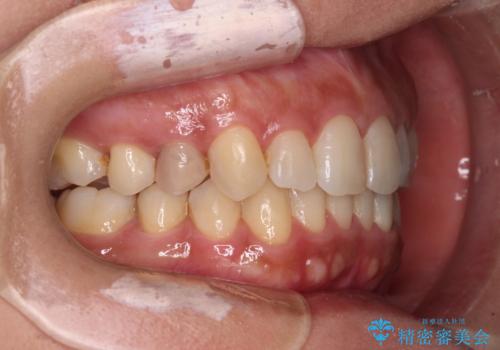

沖縄から飛行機で通院 インビザラインによる矯正治療

- 患者様

- 30代女性

- 矯正装置

- インビザライン

- 定期的に東京に来るので、沖縄から矯正治療で通院したいとのことで来院された患者様です。

歯列不正は軽度であったので、応急処置の少ないインビザラインにて矯正治療を行うこととしました。